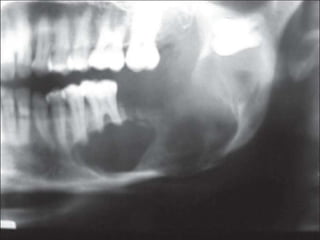

Case

 18 year-old female with several month history of lesion

Case  18 year-oldfemale with several month history of lesion in right maxilla, treated initially by oral surgeon with multiple curettage.  Has experienced recent onset of rapid expansion, with complaints of loose dentition and pain.